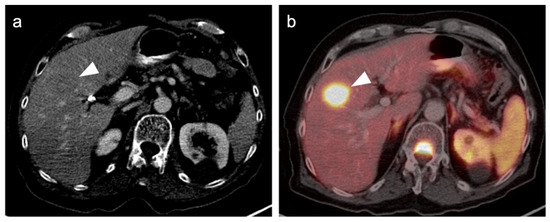

- Orcurto, V.; Denys, A.; Voelter, V.; Schalenbourg, A.; Schnyder, P.; Zografos, L.; Leyvraz, S.; Delaloye, A.B.; Prior, J. 18F-fluorodeoxyglucose positron emission tomography/computed tomography and magnetic resonance imaging in patients with liver metastases from uveal melanoma. Melanoma Res. 2012, 22, 63–69. [Google Scholar] [CrossRef] [PubMed]